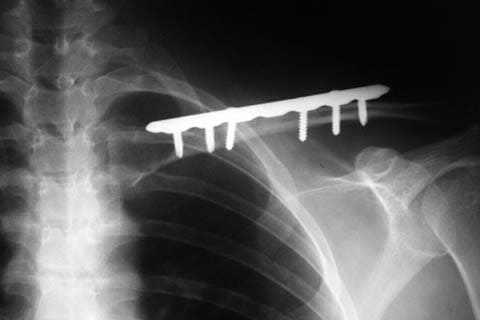

При открытых и многооскольчатых переломах, при повреждении подключичной артерии и нервов, а также при переломах со значительным смещением всегда производится вправление оперативным путем, с фиксацией спицами или пластиной. После операции накладывается гипсовая повязка на 4-6 недель. Спицы удаляются из ключицы спустя 2-3 месяца, пластина может находиться до 1 года и более.

Фиксация отломков при переломе ключицы, ренгенография после операции остеосинтеза